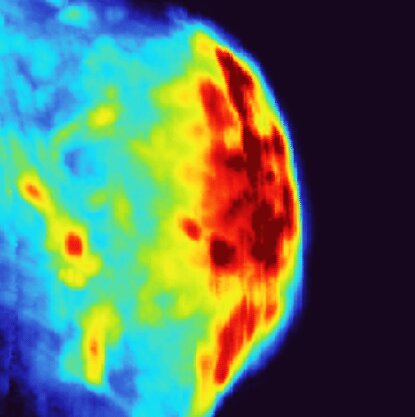

Красный цвет на фотоакустическом изображении показывает, где накопились золотые нанозвёзды в опухоли мочевого пузыря. Автор: Science Advances (2025). DOI: 10.1126/sciadv.adx6350

Каннинг и Ву проверили эффективность своей системы на модели рака мочевого пузыря у мышей, используя усовершенствованную версию золотых нанозвёзд. Новый дизайн Каннинга заключает каждую нанозвезду в полую золотую оболочку, которая стабилизирует её «лучи» при нагреве, предотвращая превращение в сферы.

В сочетании с системой PACT Ву команда легко смогла обнаруживать и визуализировать нанозвёзды, а также контролировать процесс фототермического лечения. Благодаря более точному мониторингу температуры исследователи определили оптимальную дозу нагрева для активации нанозвёзд и уничтожения клеток.

Комбинация этих технологий привела к 100% выживаемости в моделях рака мочевого пузыря, при этом не наблюдалось токсичности или повреждения поверхностных тканей.